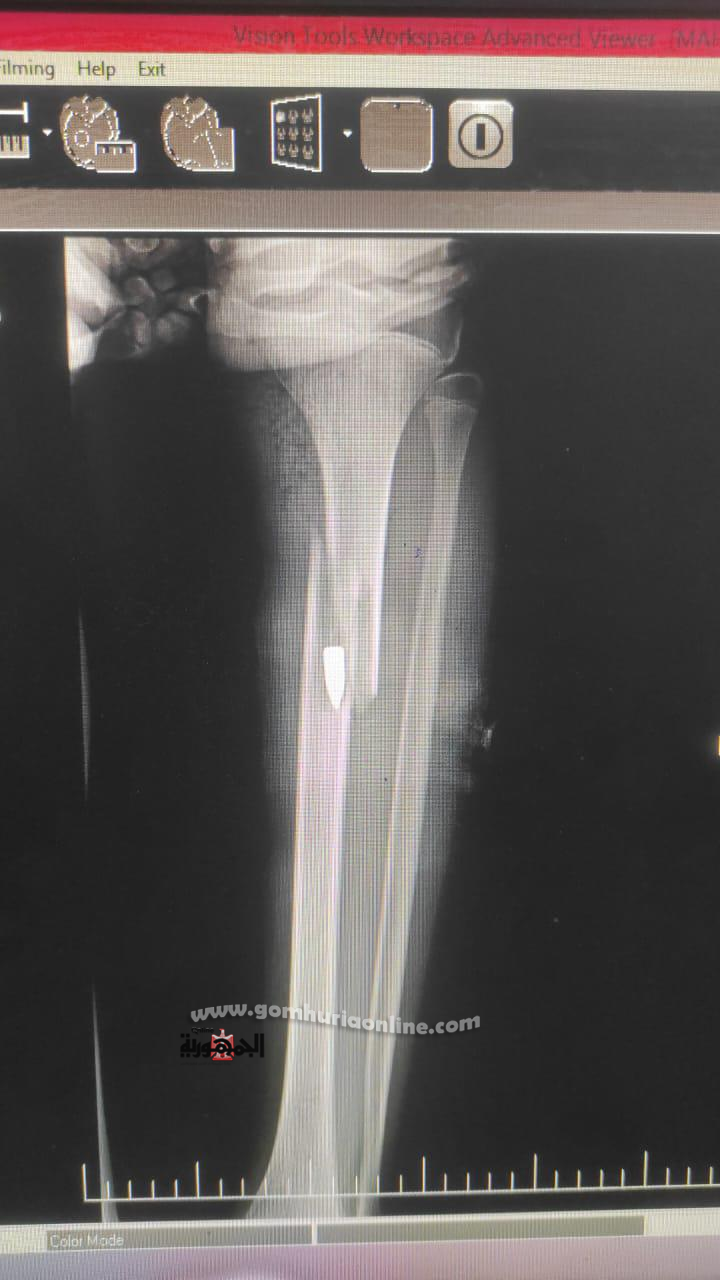

وكان المصاب وصل إلى استقبال قسم العظام في تمام الساعة 9:35 صباحًا من يوم الجمعة الموافق 6 يونيو 2025، وتم التعامل معه وفق البروتوكولات الطبية، حيث أُجريت له الفحوصات والإشعاعات اللازمة، وتبين وجود طلق ناري مستقر داخل تجويف العظم دون فتحة خروج، بالإضافة إلى كسر مفتوح، مع عدم وجود تهتك في الأعصاب أو الأوعية الدموية، وهو ما ساعد في الحفاظ على سلامة الطرف المصاب.

تم تقديم الإسعافات الأولية وتثبيت الكسر مؤقتًا بجبيرة، ثم نُقل المصاب إلى القسم الداخلي للعظام، حيث تلقى الرعاية الطبية والمتابعة لحين تجهيزه للعملية، مع إجراء الغيارات اليومية على الجرح لضمان نظافته حتى لا يؤثر على إجراء العملية، وبعد استكمال الفحوصات، أُدرج على جدول العمليات، وخضع لجراحة دقيقة شملت استخراج الطلق، وتنظيف موضع الإصابة، ورد الكسر، وتثبيته باستخدام مثبت خارجي.